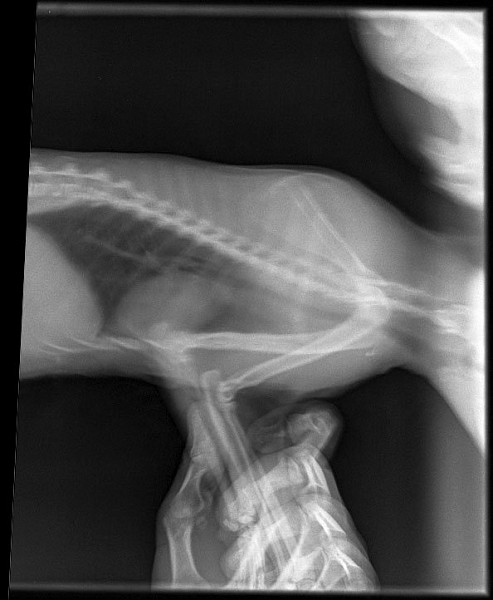

Сделали 3 рентгеновских снимка:

http://www.imageup.ru/img14/3262898/2019-01-18-pestrushka-02.jpg

http://www.imageup.ru/img14/3262899/2019-01-18-pestrushka-03.jpg

На снимке головного мозга кошки врач предположительно нашёл небольшие тёмные пятна справа (???), и сказал, что это расширенные сосуды по типу варикоза и они давят на мозг, в результате чего животное бьётся в судорогах. Но это неточно и нужны консультация ветеринара-невропатолога и МРТ головного мозга кошки.